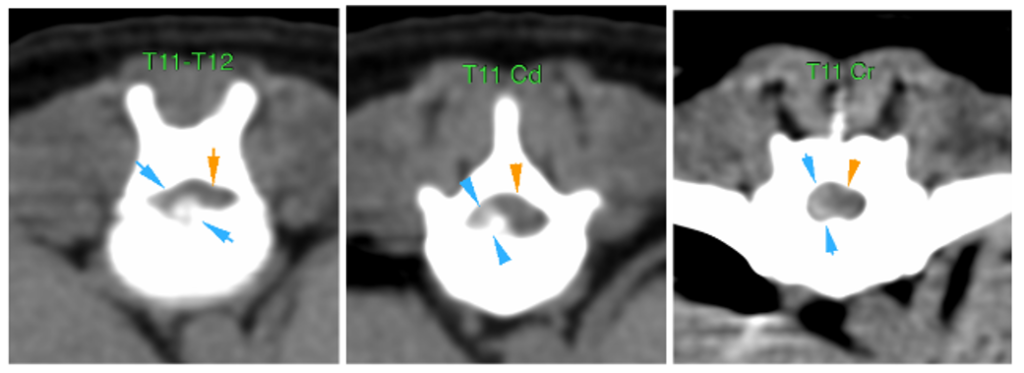

En el espacio intervertebral (IV) de T11-T12, se visualiza una lesión extradural, con presencia de material hiperatenuante (parcialmente mineralizado) localizado en el aspecto ventral del canal vertebral, lateralizado a la derecha (flechas azules).

Este material se extiende cranealmente a lo largo del cuerpo vertebral de T11 hasta su aspecto craneal, ocupando aprox. 50-70% del diámetro del canal vertebral, causando moderada/marcada compresión medular (flechas naranjas).

El material también se extiende hacia el foramen IV derecho de T11-T12.